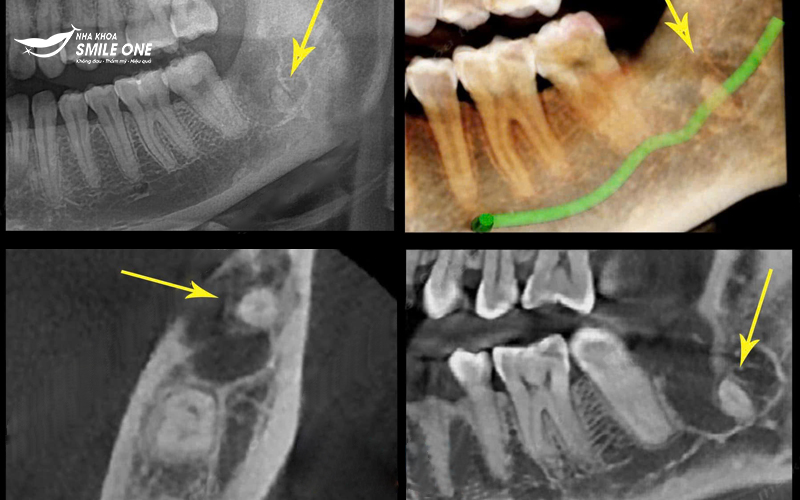

Phim chụp X quang vị trí nhổ răng để sót chân răng gây viêm nhiễm

Đau nhức kéo dài: Sót chân răng có thể tạo ra áp lực trong xương và mô mềm xung quanh, khiến bệnh nhân cảm thấy đau đớn liên tục. Điều này không chỉ làm giảm chất lượng cuộc sống mà còn làm chậm quá trình hồi phục.

Tổn thương mô và xương hàm: Việc sót chân răng có thể dẫn đến tổn thương xương hàm, làm suy yếu cấu trúc xương. Điều này có thể gây khó khăn trong việc phục hồi sau khi nhổ răng và ảnh hưởng đến các thủ thuật nha khoa sau này như cấy ghép implant.

Khi thực hiện thủ thuật nhổ răng khôn, nếu bác sĩ không lấy hết phần chân răng còn sót lại trong xương hàm, tình trạng này có thể dẫn đến nhiều biến chứng nguy hiểm khôn lường. Chân răng còn sót lại có thể gây nhiễm trùng, đau nhức làm cho vùng nhổ răng không thể lành thương lại được.

Viêm nhiễm và nhiễm trùng tái phát: Chân răng sót lại có thể là nơi tích tụ vi khuẩn, gây viêm nhiễm. Viêm có thể dẫn đến sưng tấy, đau nhức, và đôi khi là nhiễm trùng nặng nếu không được xử lý kịp thời.